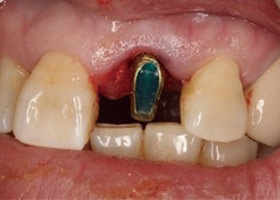

植牙後,立即利用舊牙套轉換成臨時性假牙。

植牙後,裝上臨時性假牙X光片。